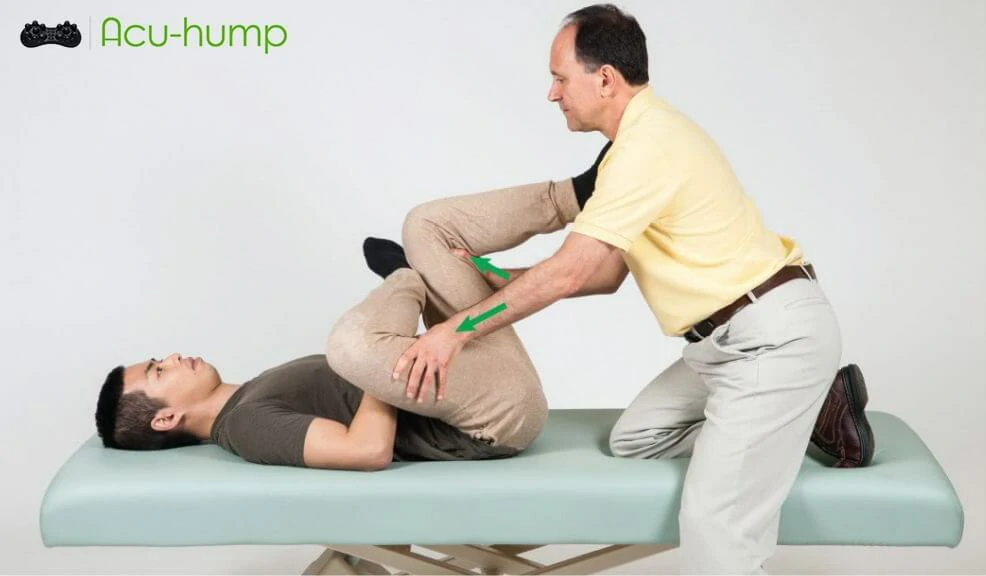

Diagnosis of Piriformis Syndrome involves a physical examination, where the doctor may check for tenderness in the buttock area. Imaging tests such as an MRI or X-ray may also be used to rule out other conditions, and electromyography (EMG) may be performed to check the muscle activity.

In addition to rest and immobilization, physical therapy is often recommended as an effective treatment for piriformis syndrome.

Physical therapy may involve a combination of exercises to stretch and strengthen muscles in the affected area.